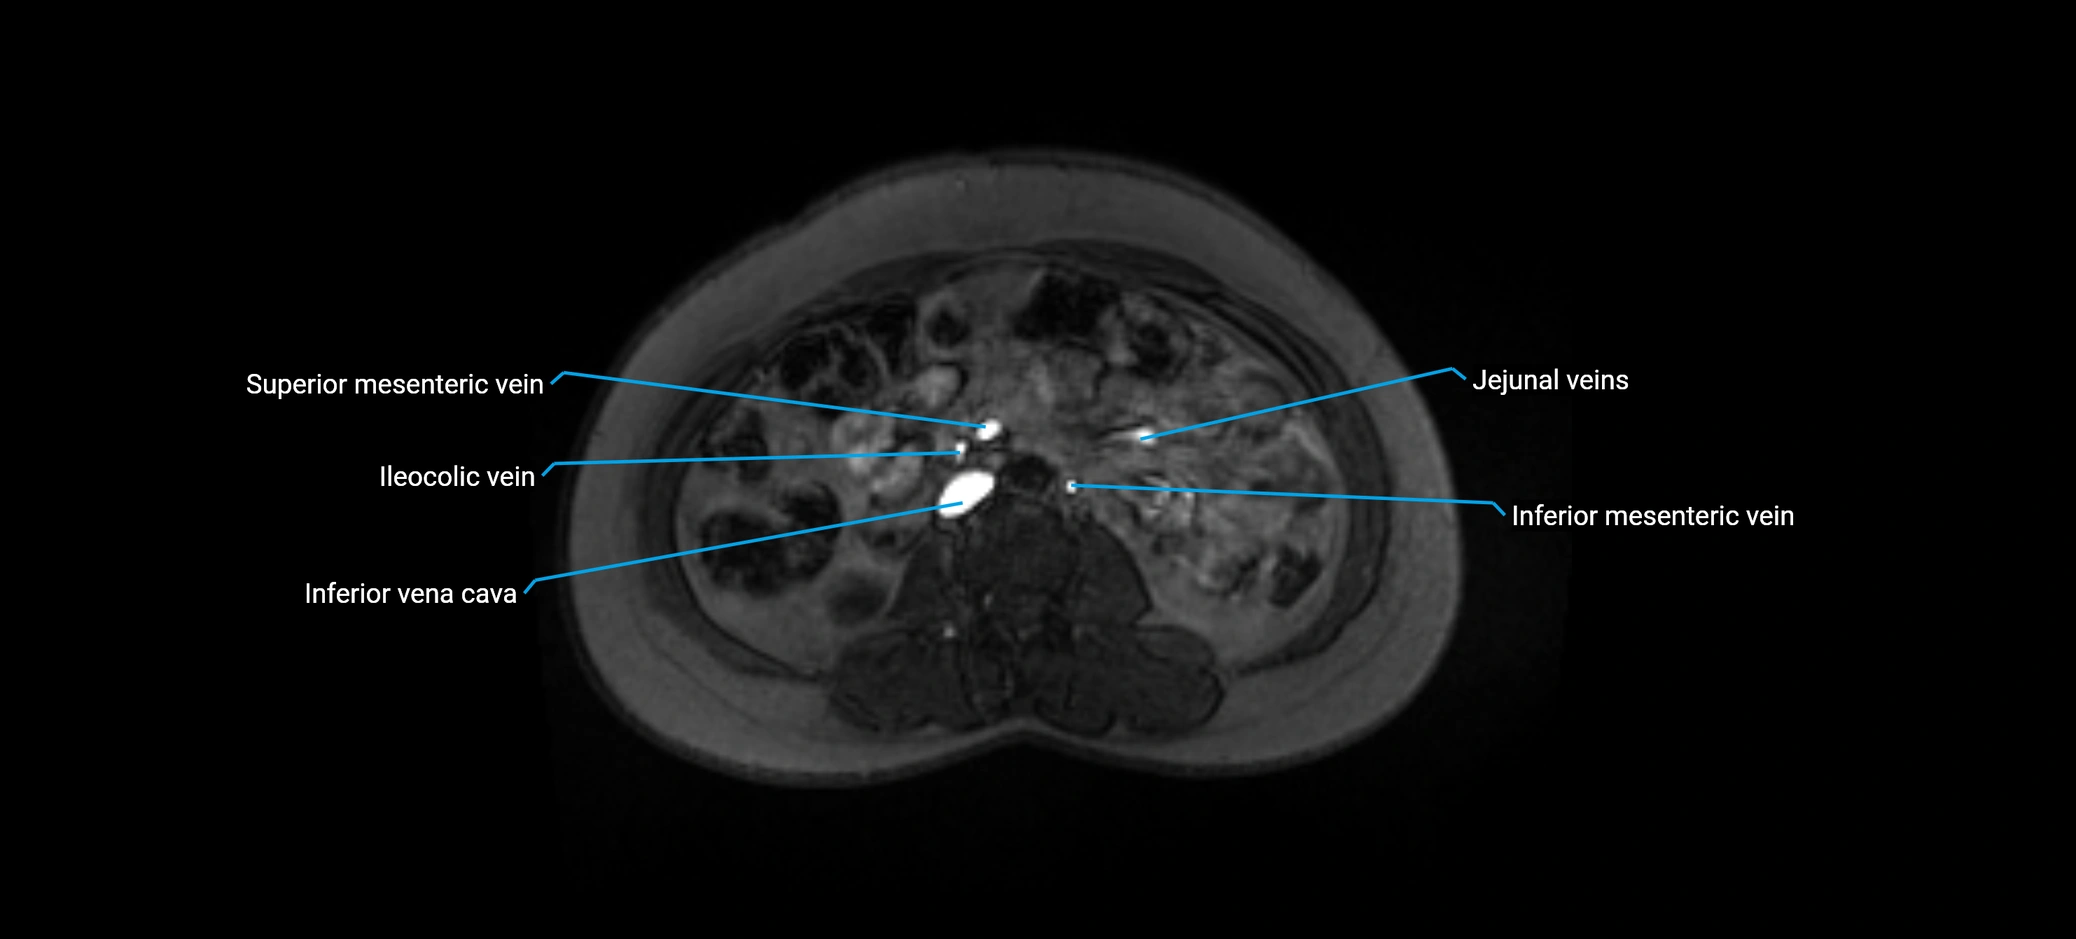

MRV TOF (Time-of-Flight MR Venography):

• Appears as a bright, high-signal vascular channel representing flowing blood

• Clearly shows branching pattern of right portal vein into anterior and posterior branches

• Best in coronal or axial reconstructions for segmental mapping

• No need for contrast, relies on flow-related enhancement

MRI image

image